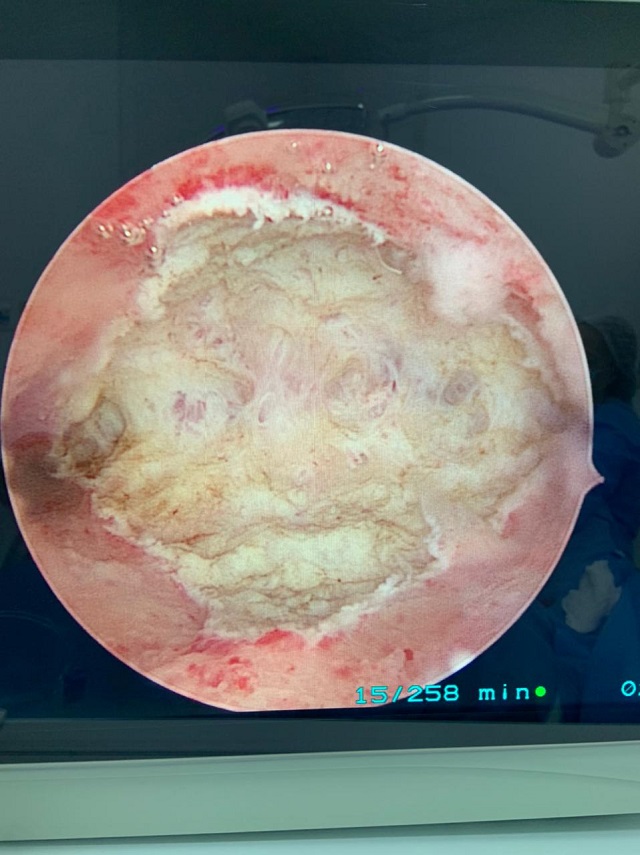

A ablação endometrial trata-se da retirada da camada mais interna do útero, o endométrio, que dá origem a menstruação. Consequentemente, o objetivo desta cirurgia é interromper o fluxo menstrual. Para determinar a necessidade do procedimento cada caso deve ser avaliado de maneira individualizada.

- Pacientes com alto fluxo menstrual que querem reduzir o fluxo a níveis dentro da normalidade de maneira definitiva devem ser informadas de que o procedimento, bem executado, causará infertilidade.

- Pacientes no período da pós-menopausa podem realizar o procedimento de maneira complementar com a finalidade de reduzir a recorrência de espessamentos endometriais anormais.